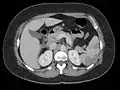

![]() | |

| Blood clots in the ventricle found on autopsy |